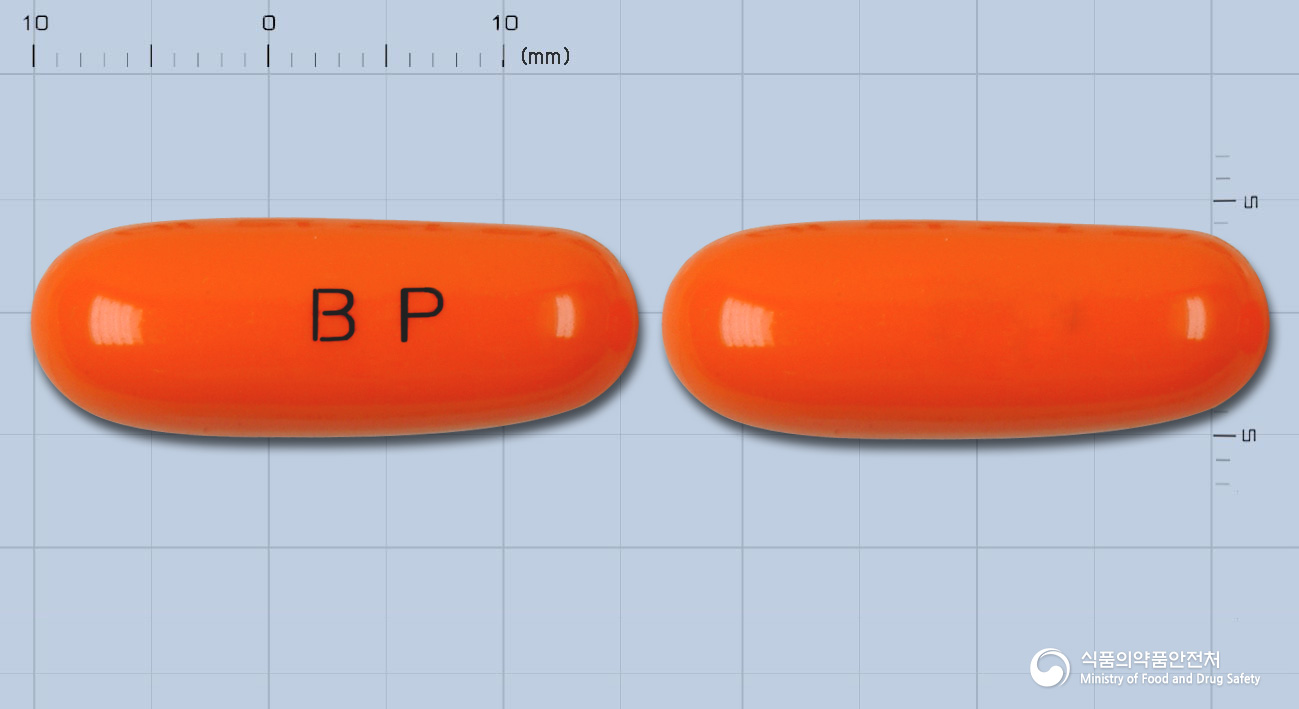

습진, 여드름, 갈라지는 손톱까지! 셀라인연질캡슐500밀리그램(엘시스틴) 효능과 복용법